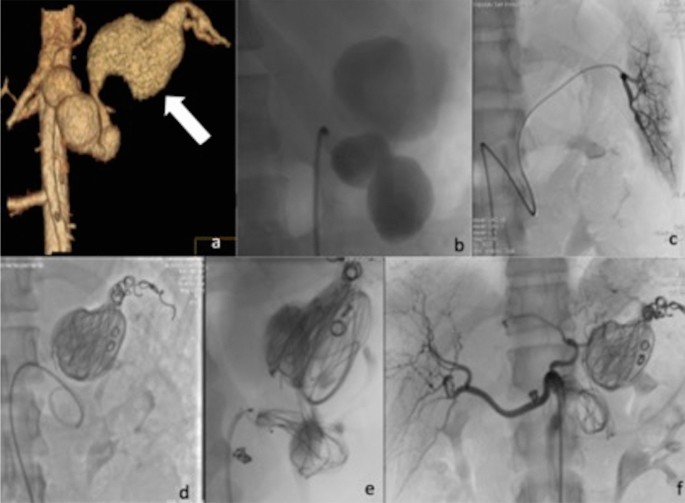

Access was obtained via the right femoral access in all but one case where a left axillary access was retained as more suitable approach. Access sheath diameter ranged from 6 to 9 Fr. In eight cases the strategy that was adopted consisted in embolization of the distal feeding branch or “back door” and the proximal feeding vessel or “front door” of the lesion. Embolization of the aneurysmal sac was also performed in six of these cases, however not with the aim of complete embolic packing, as the size of the aneurysm was very large (Fig. 1). A large number and extensive variety of embolic materials (and their combination) were used for those eight cases. In particular pushable coils [Tornado and Jackson coils (Cook Medical, Bloomington, Indiana, USA), and Vortx (Boston Scientific, Natick, USA)], vascular plugs [Amplatzer Vascular Plugs (AGA, Plymouth, USA) and POD- Penumbra Occlusion Device (Penumbra, Inc., Alameda, California, USA), liquid embolics [Ethylene–Vinyl Alcohol Copolymer (Onyx LES, Covidien, Paris, France)—in a case that was also previously reported as case report13- and Nbutyl- cyanoacrylate (Glubran II, GEM, LU, Italy)] and – in the early days- even fragments from the Teflon-coating of an angiographic guidewire. In the remaining three cases, exclusion of the sac was obtained with the placement of one or more covered stents (Viabahn, W.L. Gore, Flagstaff, AZ, USA); an example is illustrated in Fig. 2.

(a) Volume rendering contrast enhanced CT confirming the presence of multilobed fusiform splenic artery GVAA measuring 88 × 140 mm (arrow). (b) Angiogram confirmed the CT findings. (c) Selective catheterization of the distal splenic artery of “back door” of the aneurysm. (d,e) Endovascular exclusion was obtained by transcatheter “sandwich” embolization with Tornado coils (Cook Medical, Bloomington, Indiana, USA) and Jackson coils (Cook Medical, Bloomington, Indiana, USA) of the distal and proximal tract of the main artery and packing of the sac. Furthermore, inflow was totally stopped using a 8 mm detachable vascular plug (Amplatzer Plug, AGA, Plymouth, USA) in the proximal neck of the aneurysm. (f) Angiogram from the coeliac axis confirming satisfactory exclusion of the GAA.